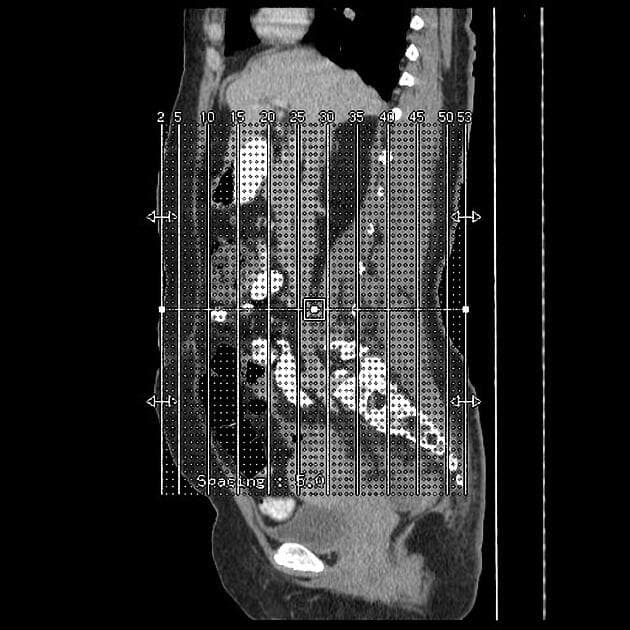

Series (8)

Axial T1